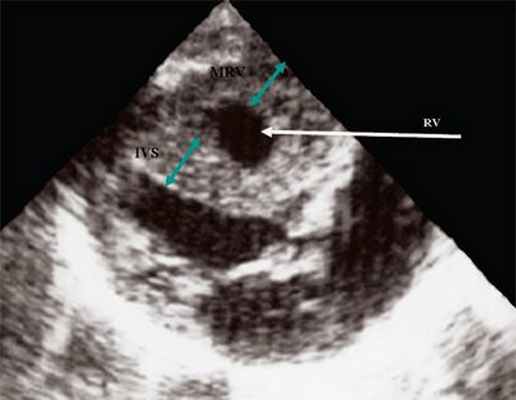

Нагрузка сопротивлением возникает при ситуации, когда выброс крови из желудочков сердца в магистральные сосуды затруднен на уровне полулунных клапанов (стеноз аорты и легочной артерии), подклапанного пространства (идиопатический гипертрофический субаортальный стеноз, подклапанный стеноз аорты или легочной артерии), на протяжении сосудистого русла (коарктация аорты) либо при значительном увеличении выходного сопротивления (синдром Эйзенменгера). В результате затруднения выброса крови резко возрастает напряжение миокарда соответствующего желудочка при относительно стабильном объеме крови, что служит проявлением систолической перегрузки сердца. При систолической перегрузке желудочков сердца независимо от нозологической формы порока полость желудочка, несущего основную нагрузку сопротивлением, умеренно увеличивается в размерах. В ответ на нагрузку сопротивлением на эхокардиограмме выявляется гипертрофия миокарда соответствующего желудочка, и чем больше сопротивление выбросу, тем резче выражена степень гипертрофии миокарда соответствующего желудочка и межжелудочковой перегородки (рис. 1) [3].

Рис. 1. Систолическая перегрузка правого желудочка. Поперечное сечение желудочков сердца при стенозе легочной артерии. Градиент давления правый желудочек - легочная артерия равен 200 мм рт.ст. Выраженная гипертрофия межжелудочковой перегородки и миокарда передней стенки правого желудочка.

Характерными особенностями выраженной объемной перегрузки правого желудочка являются дилатация желудочка, при которой толщина миокарда не превышает верхней границы нормы, увеличение правого предсердия, парадоксальный характер движения межжелудочковой перегородки и увеличение амплитуды движения трикуспидального клапана (рис. 2, 3).

Рис. 2. Длинная ось сердца. Объемная перегрузка правого желудочка при дефекте межпредсердной перегородки. Объем сброса крови превышает 200% МОС. Отмечается выраженная дилатация правого желудочка.

Рис. 3. Объемная перегрузка правого желудочка при дефекте межпредсердной перегородки. В- и М-сканирование. Стрелкой показан парадоксальный характер движения межжелудочковой перегородки.

IVS - межжелудочковая перегородка, MLV - миокард левого желудочка, LV и RV - левый и правый желудочек.